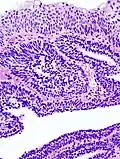

Additional image

An inverted papilloma, also known as Ringertz tumor,[1] is a type of tumor in which surface epithelial cells grow downward into the underlying supportive tissue. It may occur in the nose and/or sinuses or in the urinary tract (bladder, renal pelvis, ureter, urethra). When it occurs in the nose or sinuses, it may cause symptoms similar to those caused by sinusitis, such as nasal congestion. When it occurs in the urinary tract, it may cause blood in the urine.

Inverted papillomae were first described by Nils Ringertz in 1938.[6] He reported their microscopic appearance and their tendency to grow into the connective tissue stroma.